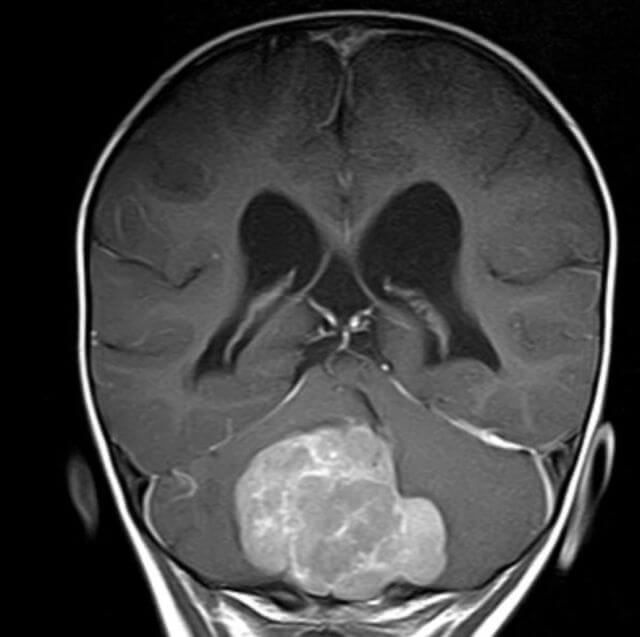

Neue Behandlungsmöglichkeit für kindliche Hirntumore

Glioblastome und ihre neuronalen Netzwerke: Neue Erkenntnisse bieten Ansatzpunkte für Therapien

Überraschender Fund bei Glioblastomen: Inseln potenter Abwehrzellen im lokalen Knochenmark

Hirntumoren bei Kindern: Krebszellen werden auf ihrer Wanderung im Tumor weniger aggressiv

Blockieren eines Eiweißmoleküls macht aggressive Hirntumoren sensibler für Strahlen- und Chemotherapie